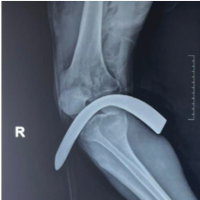

- Magnetic resonance imaging depicted mild effusion with extension into the suprapatellar bursa. A well-defined oval-shaped hyperintense fluid collection was present, 10 mm × 18 mm over the prepatellar region, with signs of bursitis.